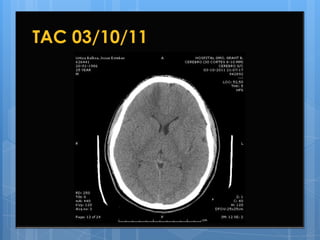

9º Día de Hospitalización

03/10/11

 Estable,  lúcido, afebril, normotenso, hemodiná

micamente estable, con mejoría clínica y

refiere alivio de cefalea. Sin fotofobia ni

mareo. Glasgow 15.

 Continúa con anosmia.

 Examen físico sin variaciones significativas.

 Se solicita nueva TAC de control.

TAC 03/10/11